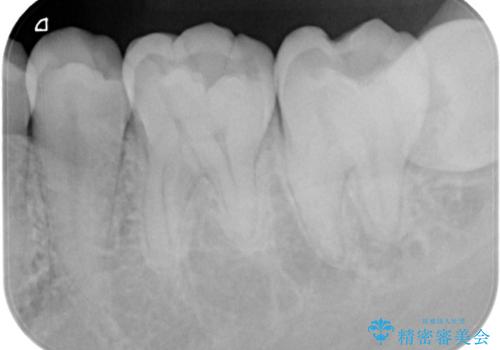

- 検査の結果、虫歯が見つかった患者様です。

白く目立たないものでの治療をご希望されたため、セラミックインレーでの治療となりました。

適合の良いセラミックインレーで修復することで見た目の綺麗さを保ったまま治療することができます。